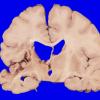

Infarct, Tract Degeneration, illustrative case (2)